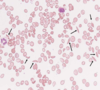

What does Wright’s Stain show?

Complete blood cell counts